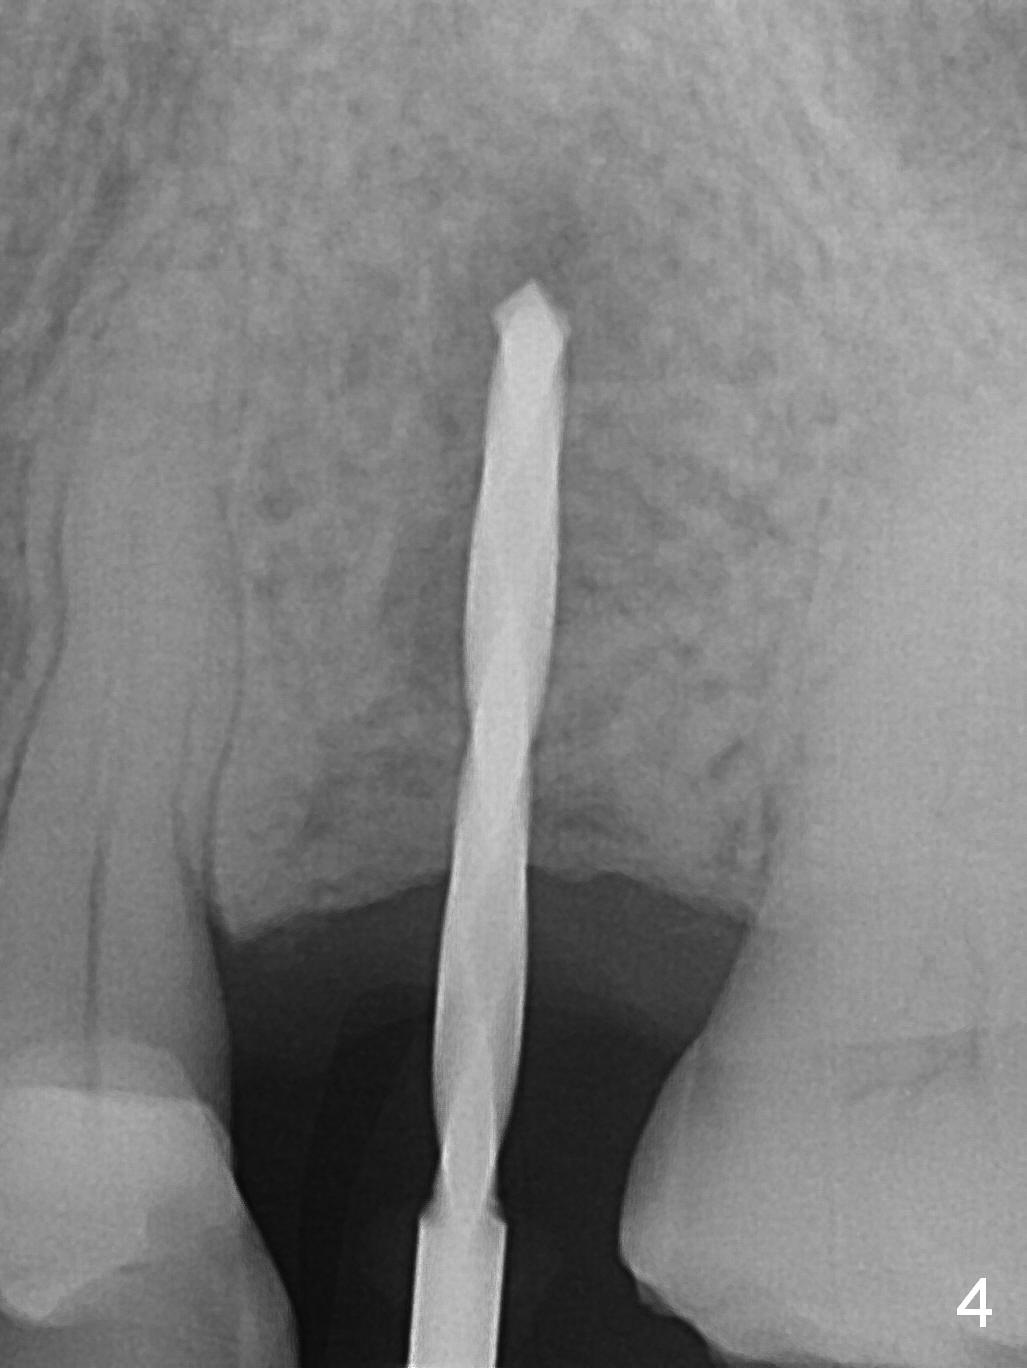

A 74-year-old man has diabetes. Implant osteointegration appears to be slow at #4, while the implant at #28 failed once. He requests implant at #13 (Fig.1). It seems that the bone is wide enough (8 mm, Fig.2 (CT coronal section) (P: palatal)) to hold a 4 mm implant (Fig.3 (axial section)). Since bone density is low at the coronal (100-200 units) and middle (50-100 units) segments (Fig.2), bone condensation will be beneficial. To facilitate wound healing, flapless approach is adopted using 1.6 mm pilot drill (Fig.4), followed by 1.4/2.6 mm bone expander. In fact there is resistance to expansion in the zone 1. Magic expander (3.0 mm) is also tried with difficulty. It appears that bone density is higher than expected. The second portion of Magic Surgical Kit is then used: 3.3 mm Magic Drill for 15 mm (gingival level, followed by Final Drill). A 4x13 mm IBS implant is seated incompletely. The osteotomy is further enlarged by 3.8 mm Magic Drill for 11 mm and deepened with 3 mm drill until 18 mm. Finally the implant is placed at a satisfactory level with insertion torque > 50 Ncm (Fig.5). A 4.5x4(3) mm abutment is placed and periodontal dressing is applied. The patient chooses to return for impression 6 months postop (Fig.6). The abutment changes to a 4x4(4) mm one. The crown is recemented nearly 2 years post cementation, which is related to distal and deep placement of the implant and bruxism (Fig.7).